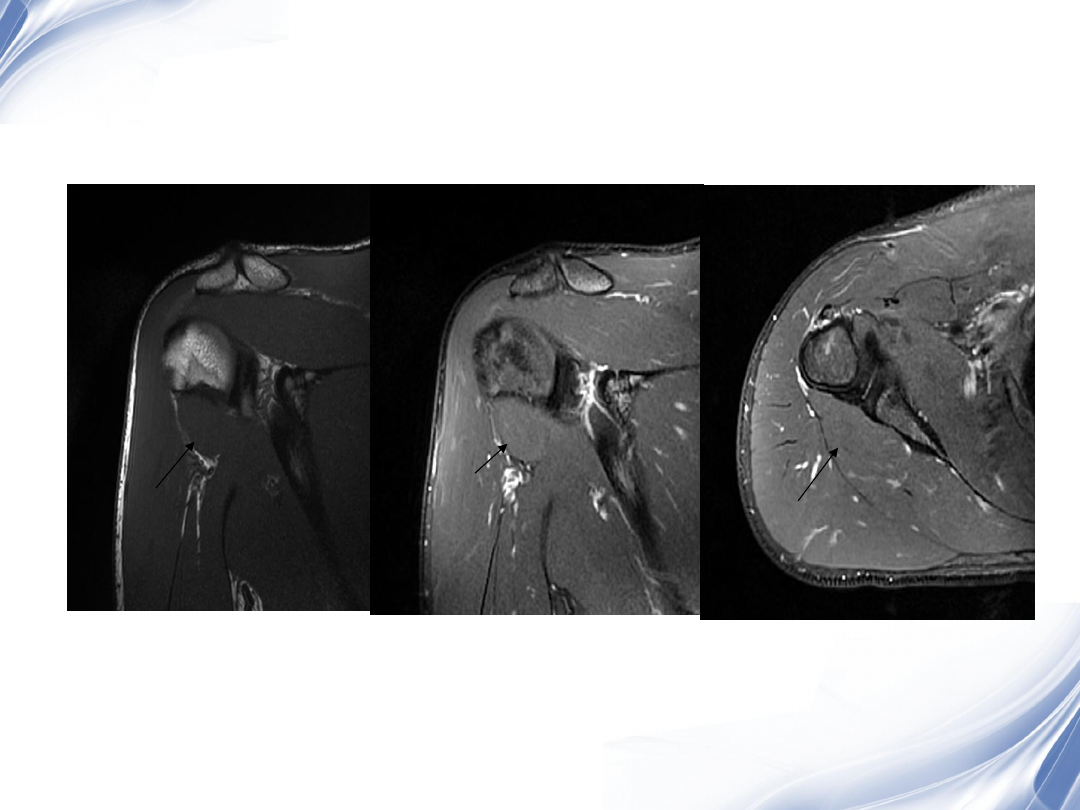

34

肩袖全层撕裂

正常MRI

background image

35